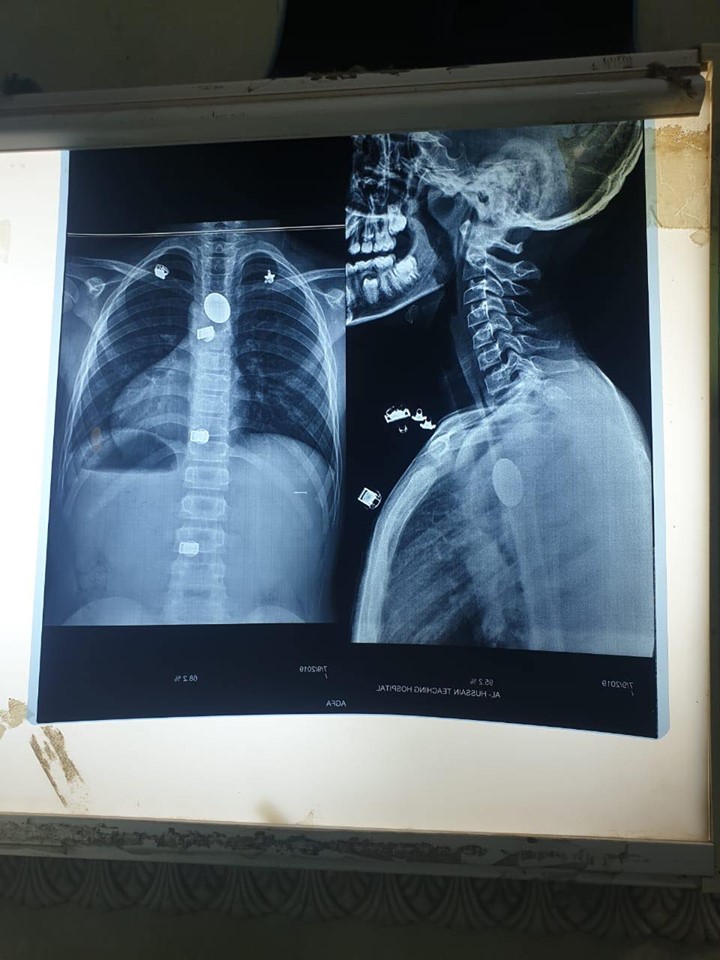

وتابع انه "بعد اخذ الفحوصات والأشعة اللازمة تبين مكان القطعة المعدنية لجئنا لاستخراجها بواسطة الناظور، وهي تقنية جديدة لاتعرض المريض لفتح البطن وتكون سريعة ولا تبعات الإفاقة من بعد العملية".